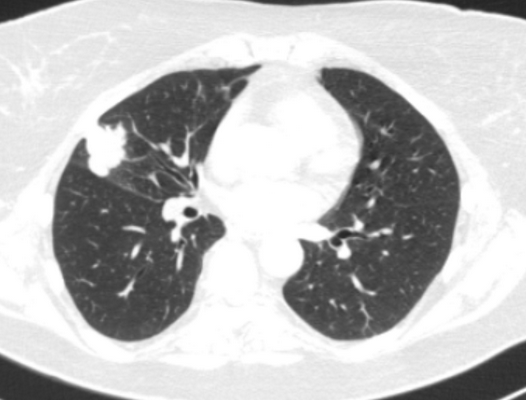

Периферический рак постепенно сформировывается в боковых отделах легких, медленно прорастая и ничем себя не обнаруживая. Данная опухоль легкого симптомы долгое время может не давать, они появляются при значительном местном распространении, вовлечении соседних органов и структур, прорастания бронхов. Диагностика рака легких этого типа локализации чаще всего возможна при профилактическом обследовании (рентгенографии или компьютерной томографии).

Фото 2 — Периферический рак (1) верхней доли правого легкого